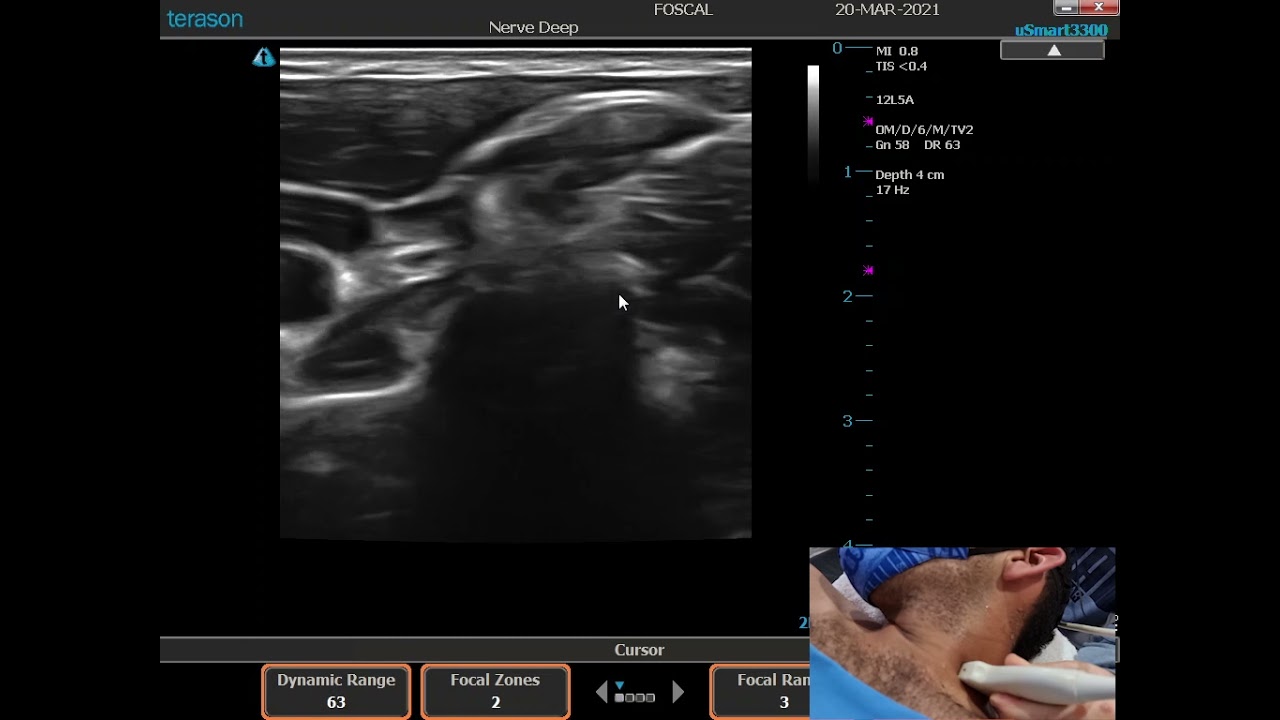

SUPRACLAVICULAR BRACHIAL PLEXUS BLOCK

Anatomical description of the brachial plexus at the supraclavicular level and its approach via the supraclavicular route